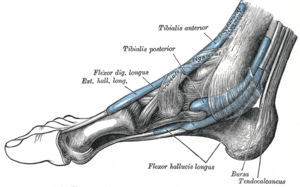

The mucous sheaths of the tendons around the ankle. Medial aspect. (Ext. hall. long. labeled at top center.) | |